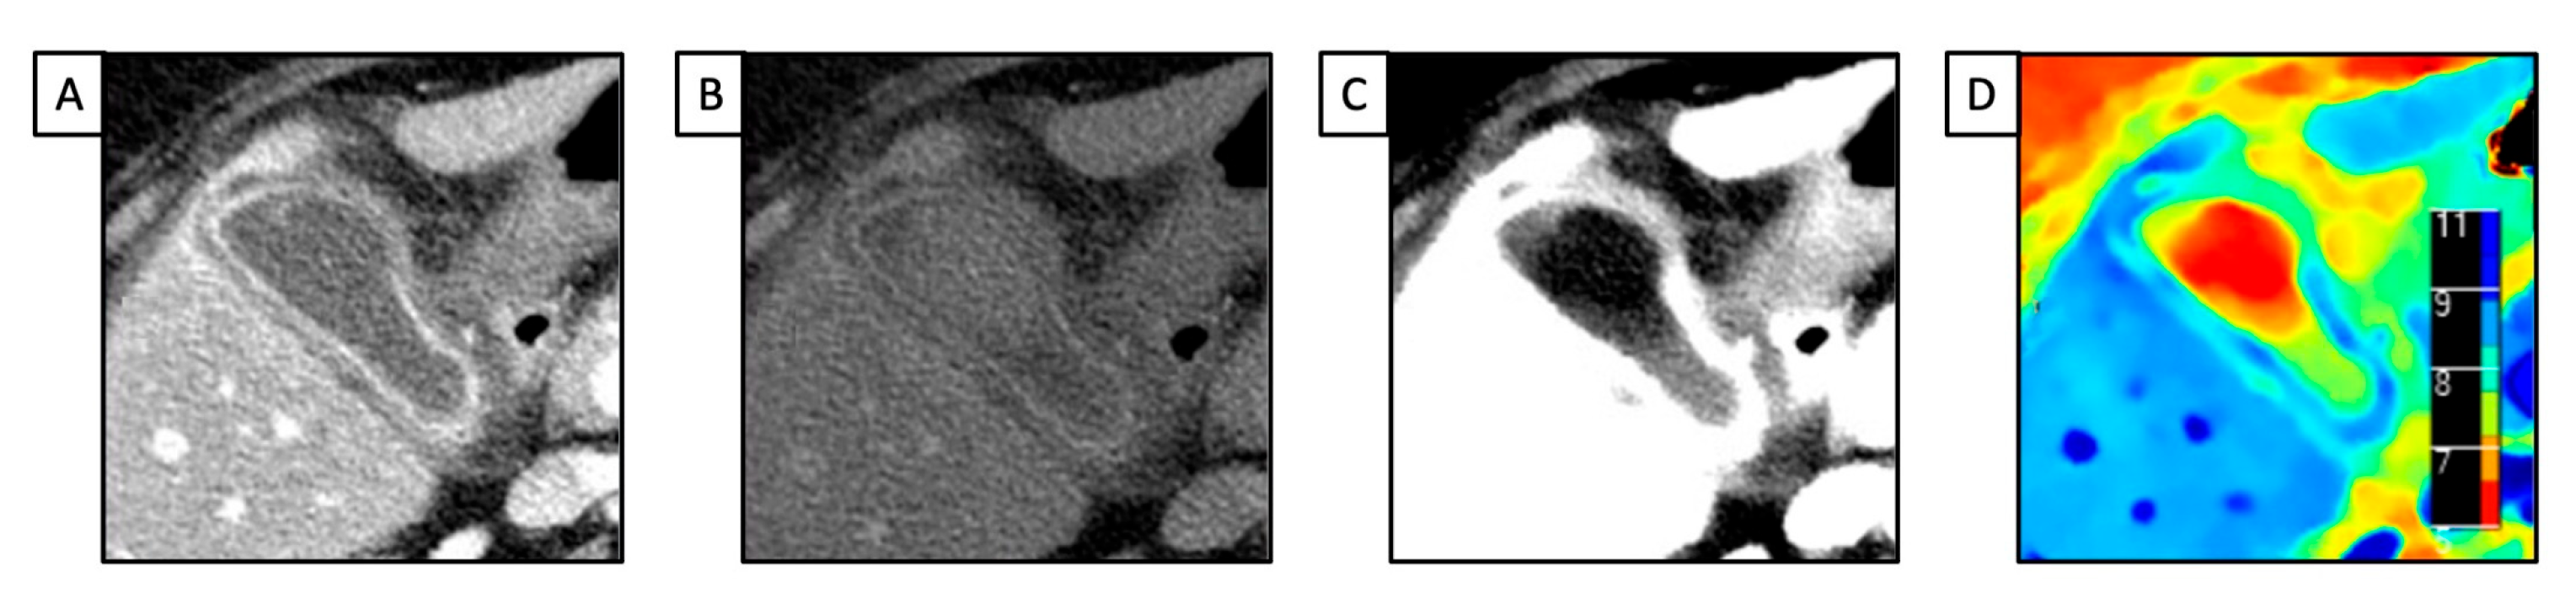

- Grosu, S.; Wang, Z.J.; Obmann, M.M.; Sugi, M.D.; Sun, Y.; Yeh, B.M. Reduction of Peristalsis-Related Streak Artifacts on the Liver with Dual-Layer Spectral CT. Diagnostics 2022, 12, 782. [Google Scholar] [CrossRef]